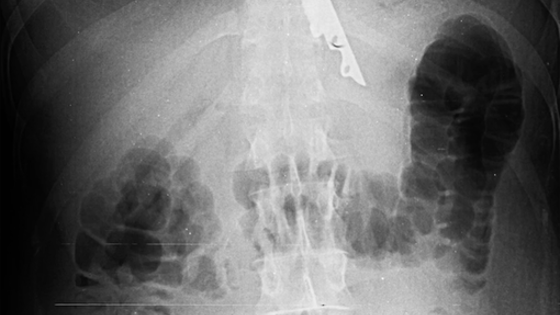

В Москве врачи спасли пациента, у которого в желудке после пикника оказался 20-сантиметровый нож. Об этом сообщает НИИ скорой помощи им. Склифосовского. По информации медучреждения, мужчина во время поедания шашлыка подавился кусочком мяса. Его друзья попытались помочь ему, протолкнув пищу ножом, однако острый предмет также оказался в пищеводе пострадавшего. В результате пострадавшего доставили в медицинское учреждение, где хирурги извлекли инородный предмет из желудка пациента. Операция прошла успешно, сейчас жизни мужчины ничего не угрожает. Врачи отметили, что случаи проглатывания посторонних предметов часто происходят как по случайности, так и в результате нелепых споров. До этого в Липецкой области врачи спасли 18-летнюю девушку с гигантской опухолью в яичнике. Она на протяжении года страдала от болей в животе, который постоянно увеличивался, и не обращалась за медицинской помощью.